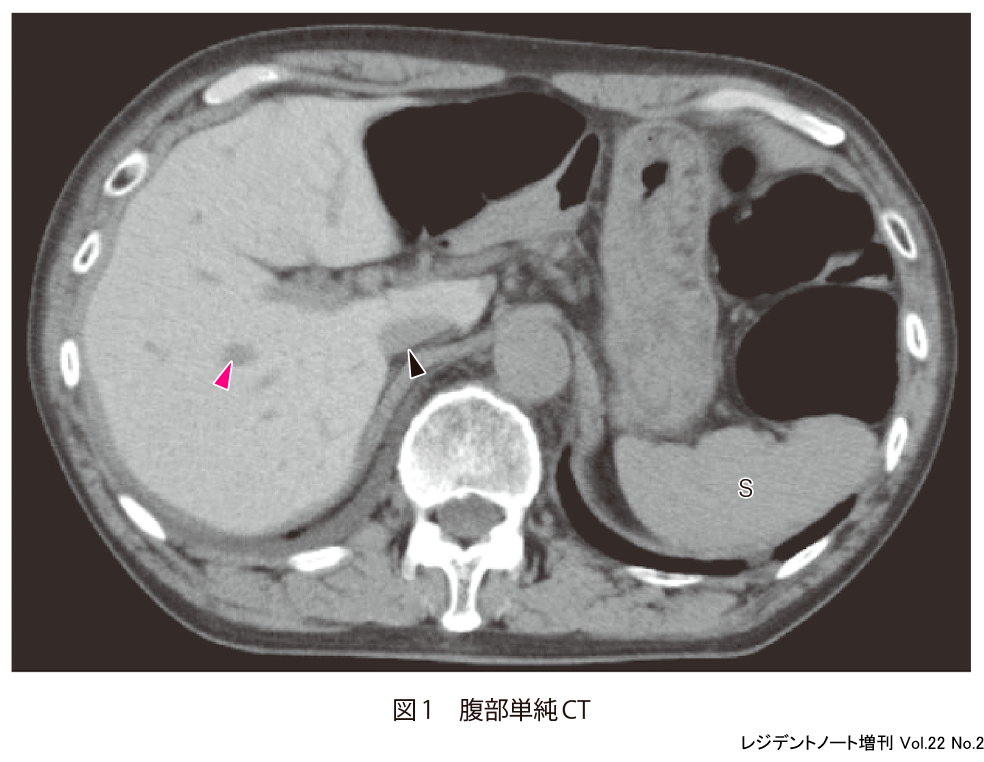

単純CTで肝実質がびまん性に高吸収に描出されている.肝実質と門脈(図1▶︎),IVC(inferior vena cava:下大静脈,図1︎▶)とのコントラストが増強しており,脾臓(図1︎ S)と比較しても肝実質が高吸収になっていることがわかる.びまん性に濃度変化を生じていると,一目では変化に気がつかないことがある.比較画像がある場合はその画像との対比を,比較画像がない場合には周囲にある構造と濃度を比較することで,変化や異常に気がつきやすくなる.今回の場合では,肝実質と肝内血管の濃度差,肝実質と脾臓の濃度差に気がつけるかどうかが最大のポイントとなる.